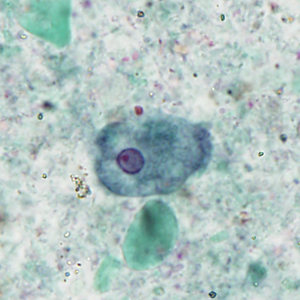

Case #404 – September 2015

A 31-year-old male presented with recurrent anal warts first noticed the summer of 2014. The warts were biopsied and diagnosed as low grade anal intraepithelial neoplasia (AIN1) in March 2015. Other symptoms included mild discomfort with defecation. In September 2015, an anal Pap smear was performed and stained with Papanicolau. Figures A–E show what was observed by the attending pathologist. The objects of interest ranged in size from 7-15 micrometers. What is your diagnosis? Based on what criteria?

Figure B